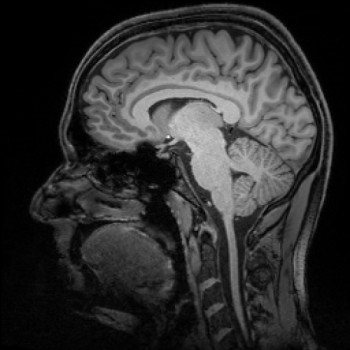

Magnetic resonance imaging provides insights into the brain. Credit: DZNE/Guido Hennes

The human brain continuously collects information. However, we have only basic knowledge of how new experiences are converted into lasting memories. Now, an international team led by researchers of the University of Magdeburg and the German Center for Neurodegenerative Diseases (DZNE) has successfully determined the location, where memories are generated with a level of precision never achieved before. The team was able to pinpoint this location down to specific circuits of the human brain. To this end the scientists used a particularly accurate type of magnetic resonance imaging (MRI) technology. The researchers hope that the results and method of their study might be able to assist in acquiring a better understanding of the effects Alzheimer’s disease has on the brain.

For the recall of experiences and facts, various parts of the brain have to work together. Much of this interdependence is still undetermined, however, it is known that memories are stored primarily in the cerebral cortex and that the control center that generates memory content and also retrieves it, is located in the brain’s interior. This happens in the hippocampus and in the adjacent entorhinal cortex.

“It is been known for quite some time that these areas of the brain participate in the generation of memories. This is where information is collected and processed. Our study has refined our view of this situation,” explains Professor Emrah Düzel, site speaker of the DZNE in Magdeburg and director of the Institute of Cognitive Neurology and Dementia Research at the University of Magdeburg. “We have been able to locate the generation of human memories to certain neuronal layers within the hippocampus and the entorhinal cortex. We were able to determine which neuronal layer was active. This revealed if information was directed into the hippocampus or whether it traveled from the hippocampus into the cerebral cortex. Previously used MRI techniques were not precise enough to capture this directional information. Hence, this is the first time we have been able to show where in the brain the doorway to memory is located.”

For this study, the scientists examined the brains of persons who had volunteered to participate in a memory test. The researchers used a special type of magnetic resonance imaging technology called “7 Tesla ultra-high field MRI.” This enabled them to determine the activity of individual brain regions with unprecedented accuracy.